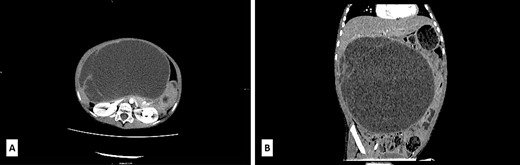

A 5-year-old boy presented with a 1-year history of abdominal discomfort and distension. Clinical examination by inspection and palpation revealed the presence of an abdominal mass that was confirmed by a CT scan. It revealed a multilocular cystic mass, with septations, filled with dense content (47−60 HU) and measured 113 × 190 × 195 mm3 (Fig. 1A). The lesion had an expansive growth but without clear liver infiltration (Fig. 1B). Differential diagnoses included mucinous cystadenoma, mesenteric lymphangioma, and hydatid cyst. A lung CT scan revealed a subpleural node in the right lower lobe, measuring 3.6 mm. Blood count test revealed elevated LDH levels of 391 U/L (range 100–190) and slightly elevated NSE level of 45.1 ng/mL (range 0–16.3) and CA 19–9 39.9 U/L (range 0–37), with normal levels of ferritin, AFP, CEA and β-HCG.

(A) Axial low-dose CT scan shows a huge cystic mass with few enhanced thin septa in the lateral aspect. Cystic space contains fluid of density 47−60HU. (B) Sagittal low-dose CT scan revealed that the cystic mass had expansive features with its cranial aspect not differentiated from the lower liver surface. No certain CT signs of liver infiltration were seen.